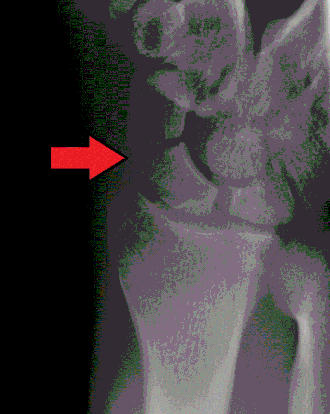

Fractuur os scaphoideum

Het os scaphoideum is moeilijk te breken. Desondanks is 60% van de breuken in handwortelbeentjes een breuk in het os scaphoideum. Het os scaphoideum is het slechtst doorbloede botje van het gehele menselijke skelet, waardoor een breuk van het botje slecht geneest. Bij een scafoïdfractuur van de hand is er vaak asdrukpijn over de duim en de wijsvinger van de aangedane hand. Bovendien is de tabatière anatomique verstreken en drukpijnlijk. Om de breuk radiologisch aan te tonen wordt vaak een zogenaamde navicularereeks geschoten, een serie röntgenfoto's van het os scaphoideum in vijf of zes verschillende projectierichtingen. Desondanks is de breuk geregeld radiologisch niet aan te tonen. Na tien tot veertien dagen gipsbehandeling wordt het klinisch en zo nodig het radiologisch onderzoek herhaald, omdat een breuk van het os scaphoideum soms na veertien dagen wel zichtbaar is op röntgenfoto's. Als behandeling wordt gedurende zes tot twaalf weken immobilisatie door middel van zogenaamd navicularegips gegeven. Dit gips reikt vanaf de elleboogsplooi tot aan de knokkels van de metacarpofalangeale gewrichten van de hand, met een verlenging tot het interfalangeale gewricht van de duim. Hiermee kan de kans op pseudartrose, een beruchte complicatie, zo klein mogelijk worden gehouden. Het gehele genezingsproces kan drie tot vier maanden in beslag nemen.